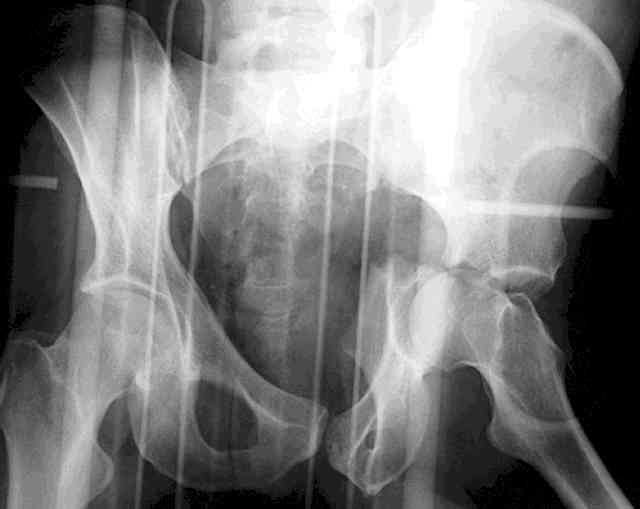

45 yo male in MVA, only other injury=small subarrachnoid bleed (neurologically fine, GCS never <14), with this transverse & associated posterior wall fx-dislocation 7/7

In skeletal traction thru distal femoral pin 40 lbs with decent reduction - except for the free fragments in the hip joint. ORIF planned for post-injury day 11.